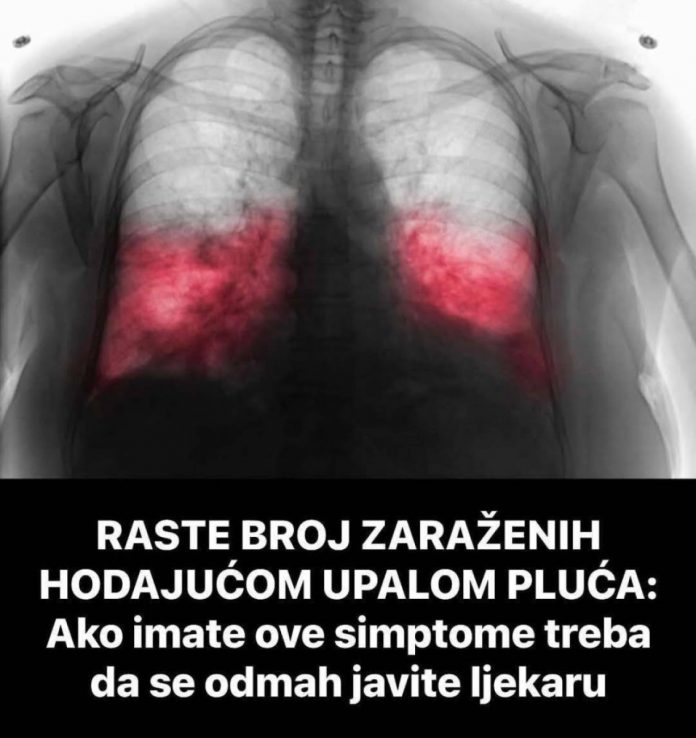

Kada postoji sumnja na hodajuću upalu pluća, ljekar će najprije razgovarati s pacijentom o simptomima i pažljivo poslušati pluća. U mnogim slučajevima potrebne su dodatne analize kako bi se potvrdila dijagnoza.

- To može uključivati laboratorijske nalaze, briseve respiratornih puteva ili rendgenski snimak pluća. Tačna dijagnoza je veoma važna, jer uzročnik ove bolesti često ne reaguje na uobičajene antibiotike koji se koriste kod drugih infekcija.